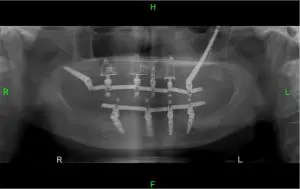

שתלים זיגומטיים אלו הם שתלים ייעודיים שמטרתם היא לאפשר ביצוע השתלות שיניים במקרים קיצונים שבהם יש בעיות קשות של מחסור בעצם הלסת העליונה.

כאשר יש מצב של חוסר עצם בלסת העליונה חסרה נקודת עיגון יציבה לשתלים.

פיתוחם של השתלים הזיגומטיים איפשר לראשונה לבצע גם במקרים כאלו שיקום פה מלא .

השתלים הזיגומטיים ארוכים יותר משתלים רגילים והם מאפשרים לעקוף את האזורים של חוסר העצם בלסת ולעגן אותם ישירות לעצם הלחי, או בשמה המקצועי עצם הזיגומה שהקנתה לשתלים אלו את שמם.

הטכניקה של השתלת השתלים הזיגומטיים לא פשוטה ויש רופאים ספורים בישראל שיודעים לבצע אותה ברמה גבוהה.

היתרון הגדול של שתלים אלו הוא ששימוש בהם מאפשר להימנע מטיפולים כואבים וארוכים ל”הכנת המטופל לטיפול” של הרמות סינוס והשלמות עצם.